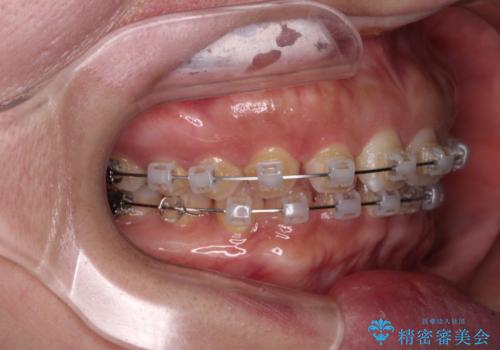

【モニター】ディープバイトを治す ワイヤー装置による矯正治療

- クリアブラケット

- 顎が疲れるほどのディープバイトを気にして来院された患者様です。

手前に傾斜している奥歯を直立させながら、歯列全体の平面を均一に整えることでディープバイトを改善していくこととしました。

ディープバイトは咬合力が強いことが特徴であり、より良い仕上がりとするために、臼歯部のコントロールを行いやすいワイヤー装置を用いて矯正治療を行うこととしました。